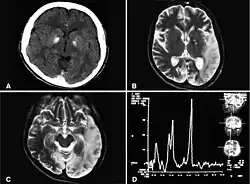

Diseases Caused by Mitochondrial tRNA Gene Mutation

Mitochondria are an organelle in the cell, which contains 22 tRNA. Gene mutation of tRNA will cause serious diseases. There are seven kinds of genes diseases caused by mitochondrial tRNA gene mutation:

1- np5601 G->A and np3243 A->G gene mutations related to MELAS (Mitochondrial encephalomyopathy, lactic acidosis, and stroke-like episodes). Most patients get this disease before 40-year-old with epilepsia and lactic acidosis. Some of them will die during 20~30 age.

2- np8363 G->A, np8356 T->C, and np8344 A->G gene mutations related to MERRF (Myoclonic Epilepsy with Ragged Red Fibers). MERRF affects central nerve system, causing epilepsia, Dementia and epicophosis.

3- np4274 T->C gene mutation related to LIMM (Lethal Infantile Mitochondrial Myopathy). Most patients are newborn, having nerve defect and lactic acidosis, and die in one month.

4- np1644 G->T gene mutation related to subacute necrotizing encephalomyelopathy (SNE). This disease is familial autosomal recessive inheritance, happened to newborn baby.

5- np606 A->G gene mutation related to Rhabdomyolysis. Toxin produced by muscle cells is the main reason that causes Rhabdomyolysis.

6- np4500 G->A gene mutation related to the splenic lymphoma. The splenic lymphoma is a common malignant tumor happened on spleen. Normally, the splenic lymphoma caused by advanced stage lymphoma transfer.

7- np4336 A->G, np15927, and np15928 gene mutations related to Parkinson's Disease and Alzheimer’s Disease. Parkinson's Disease is a degenerative disorder of the central nervous system.